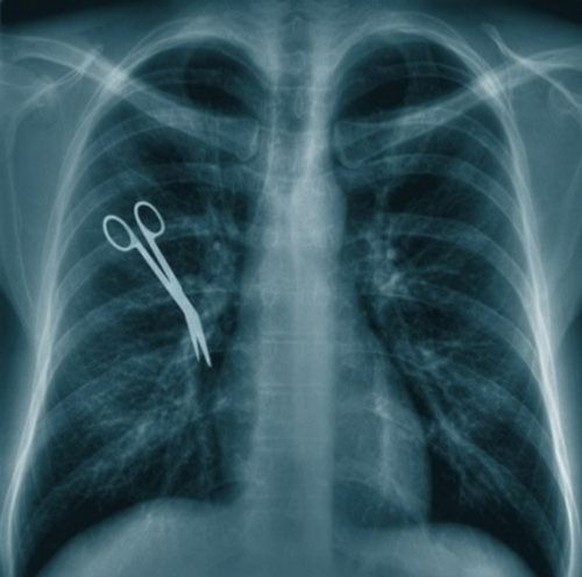

Die Operation lief scheinbar nicht wie gewünscht.